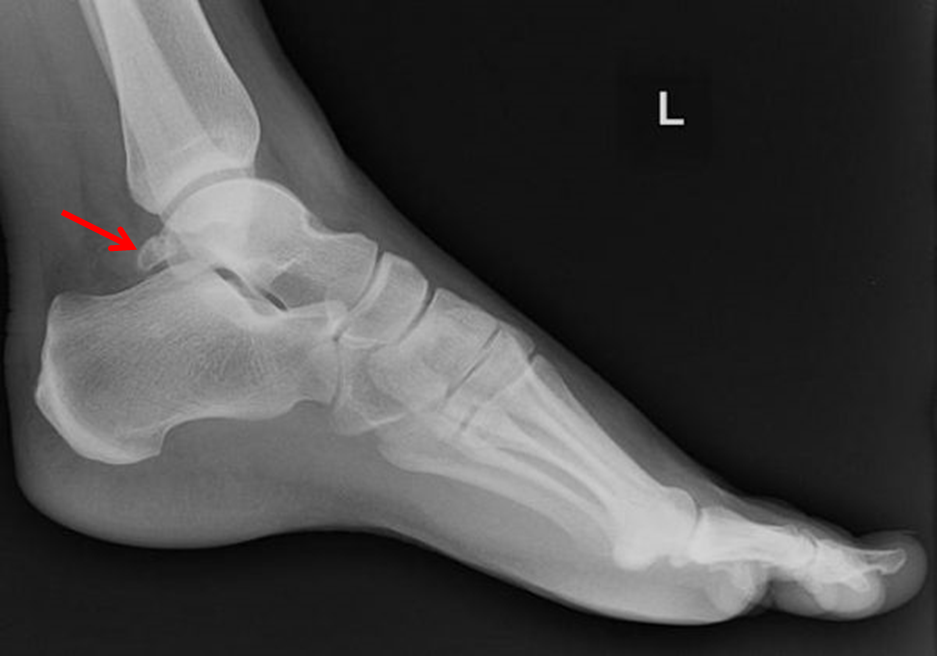

Hình ảnh gai sau xương sên trên X Quang

Hình 1: Bệnh nhân Nam 28 tuổi

Hình ảnh sau mổ trên X quang và vết mổ

Hình 2: Bệnh nhân Nam 45 tuổi

A: Hình ảnh khối gai xương trên X quang trước mổ (mũi tên đỏ)

B: Hình ảnh khối gai xương trong nội soi (mũi tên đỏ) và hình ảnh viêm gân gấp dài ngón cái và bao khớp sau

C: Hình ảnh X quang sau mổ